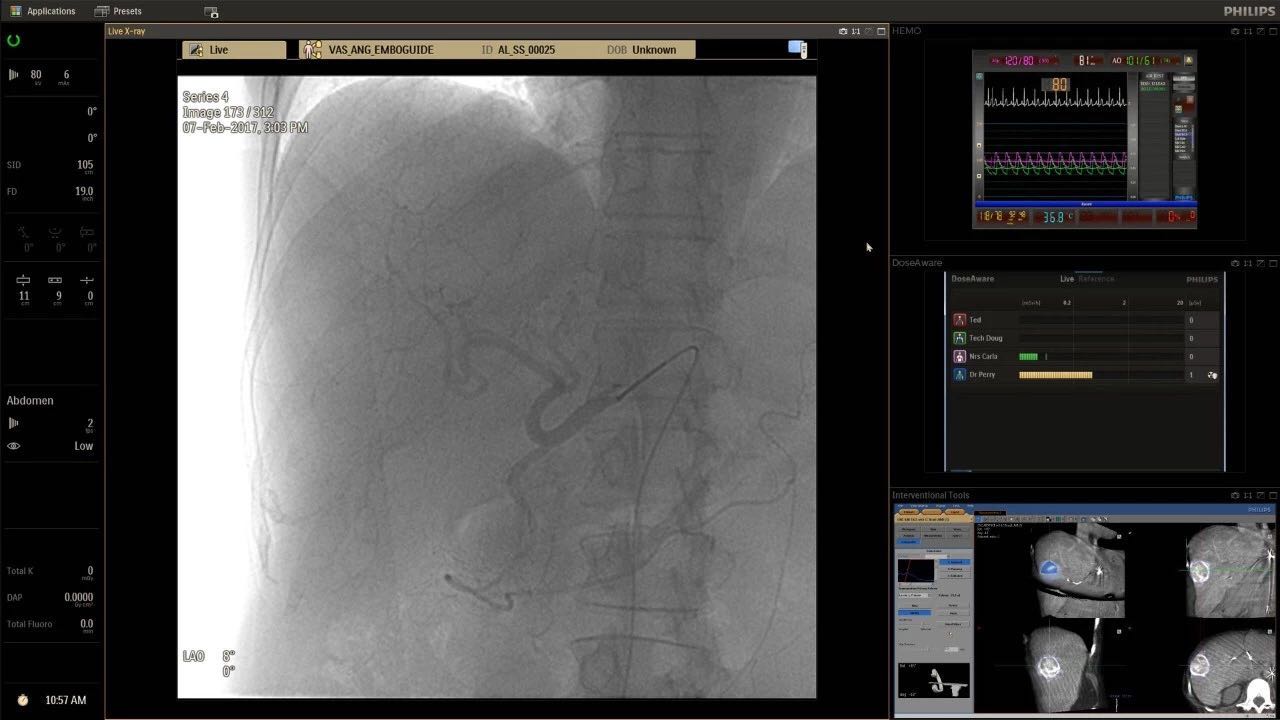

在日益復(fù)雜的干預(yù)期間,臨床醫(yī)生需要快速、輕松地可視化關(guān)鍵解剖結(jié)構(gòu)并確定手術(shù)過程中患者的變化。2019年1月17日,飛利浦宣布推出采用FlexArm的Azurion 7 C20,旨在提高圖像引導(dǎo)程序的定位靈活性。

帶有FlexArm的Azurion 7 C20 包含一系列創(chuàng)新技術(shù),使臨床醫(yī)生可以更輕松地在整個患者身上進(jìn)行二維和三維成像。當(dāng)臨床醫(yī)生移動系統(tǒng)時,圖像光束自動保持與患者的對準(zhǔn),允許更一致的可視化并使他們能夠?qū)⒆⒁饬性谥委熒稀?/span>

(FlexArm C型臂可以沿著工作臺的兩側(cè)提供偏心成像。這允許醫(yī)生在左臂或右臂上進(jìn)行徑向進(jìn)入病例,完全或部分伸展,而無需移動患者或樞轉(zhuǎn)桌子。X射線束與手臂保持對齊,以促進(jìn)其整個長度的平滑導(dǎo)航,而無需進(jìn)行持續(xù)調(diào)整。)

飛利浦表示,采用FlexArm設(shè)計的Azurion 7 C20可提供卓越的靈活性和直觀的控制。該系統(tǒng)由智能運動引擎驅(qū)動,可在八個不同的軸上移動,所有這些軸均由其單個“Axsys”控制器控制。臨床醫(yī)生的模擬測試表明,該系統(tǒng)有可能顯著減少患者,工作人員和設(shè)備的重新定位,從而改善微創(chuàng)手術(shù)的可及性,包括通過患者手腕進(jìn)入身體的手術(shù)(橈動脈入路),并降低患者的風(fēng)險。無意中拔出電線和管子,以及節(jié)省大量時間。該系統(tǒng)非常適合混合手術(shù)室(OR),可滿足一個房間內(nèi)的多種專業(yè)需求,例如手術(shù)和血管內(nèi)手術(shù)的組合。

FlexArm在不少于8軸的情況下旋轉(zhuǎn),從而創(chuàng)建幾乎無限的靈活性來執(zhí)行成像,從頭部到腳部在左側(cè)和右側(cè)進(jìn)行2D和3D可視化。圖像光束保持與患者對齊,允許在旋轉(zhuǎn)或角度期間更好地可視化解剖結(jié)構(gòu)。使用Axsys運動控制系統(tǒng)輕松操作支架。